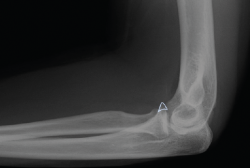

Presentamos el caso de una mujer de 46 años, diestra, sin patología crónica y que trabaja como auxiliar en una residencia geriátrica. Durante su jornada laboral sufre una caída casual presentando dolor y limitación funcional en su codo izquierdo. No presenta deformidades externas en el codo, ni lesiones vasculonerviosas. En el estudio radiológico, se sospecha una fractura de la punta de la apófisis coronoides del codo izquierdo, que correspondería, según la clasificación de Regan y Morrey, al tipo 1 (Figuras 1 y 2). Se comprueba que el codo es estable y se coloca una férula braquial, a la espera de realizar una tomografía computarizada (TC), que confirma la lesión. En la TC podemos visualizar mejor la morfología de la fractura de coronoides tanto en los cortes sagitales (Figura 3), como en los axiales (Figura 4).

Figura 1. Radiografía lateral del codo izquierdo. La silueta señalada corresponde a la fractura de la punta de la apófisis coronoides el día de la caída.